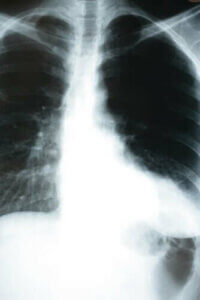

Lungebetændelse er en infektion, som påvirker alveolerne i lungerne. Dette er små sække dækket af blodårer, som udfører udvekslingen af luft. Med andre ord, er de ansvarlige for at udskille kuldioxid (CO2) og fange ilt fra det ydre. Spørgsmålet om, hvordan lungebetændelse påvirker kroppen, er så vigtigt – fordi udveksling af luft er så vigtig en proces.